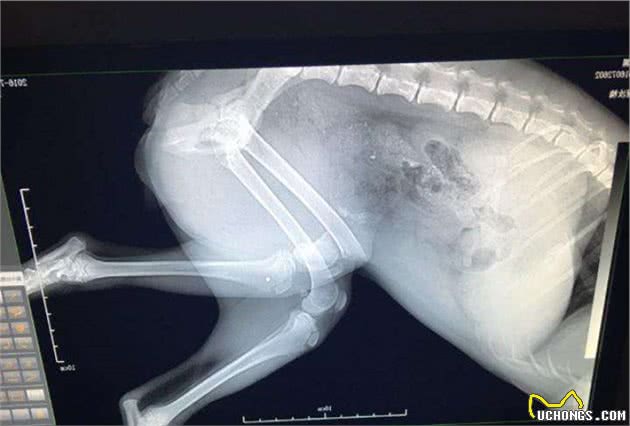

2. 影像检查

超声检查包括图像检查,CT、核磁共振、X光,但是许多铲屎官并不清楚这些检查之间有什么区别,就让兽医小明来一一说明。

如果狗狗患了外伤,譬如伤到骨头等部位,那么X光是最优先的选择,因为它出片的速度很快,但是它的缺点是没办法细致观察狗狗的情况,如果想要进一步观察的话,那么就可以选择CT检查。

如果是胸部方面的疾病,X光拍片能够粗略检查狗狗的心脏、、主动脉、肺等,但是要想结构更加清晰的话,那么胸部CT还是更好的选择,它的准确性会高于常规的X光,但是CT检查的辐射剂量会明显高于X光。